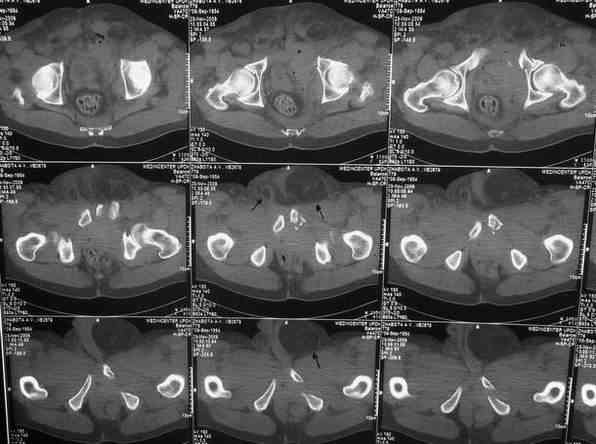

Уважаемые коллеги.У больного оскольчатые переломы левых лонной и седалищной костей со смещением, разрывом симфиза и распространением линии перелома на вертлужную впадину; переломы крыла левой подвздошной кости и правой боковой массы крестца без смещения; разрыв уретры.За последние годы пациент 6 раз оперирован на передней брюшной стенке (гнойный аппендицит срединным доступом, вентральная послеоперационная грыжа и паховые грыжи с обеих сторон, оперированные по 2 раза каждая). Остались 3 грубых втянутых рубца после этих операций. В настоящее время имеются 2-сторонние паховомошоночные грыжи (на одной из КТ-грамм указаны стрелками), из которых левая - значительных размеров. Мошонка огромная, однако, не напряженная. Состояние больного на сегодняшний день относительно удовлетворительное, кровопотеря компенсирована, мочевой пузырь катетеризирован.Прошу мнения сообщества по следующим вопросам: выполнять ли в таких условиях остеосинтез? Если да, то в какой последовательности (отдельно или одним этапом с герниотомией)? Объем остеосинтеза? Доступ?